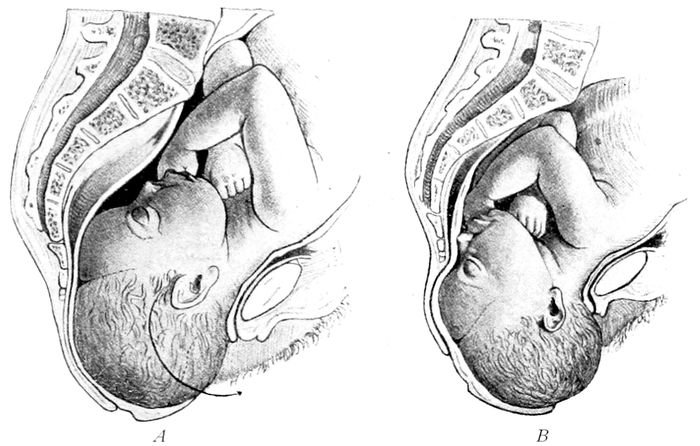

The breech. Left-sacro-anterior position |

| |

The breech. Left-sacro-posterior position |